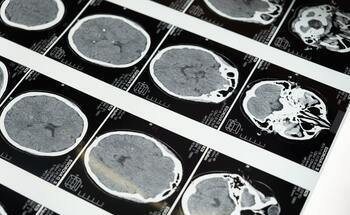

Traumatic Brain Injuries – Signs, Types, and Compensation